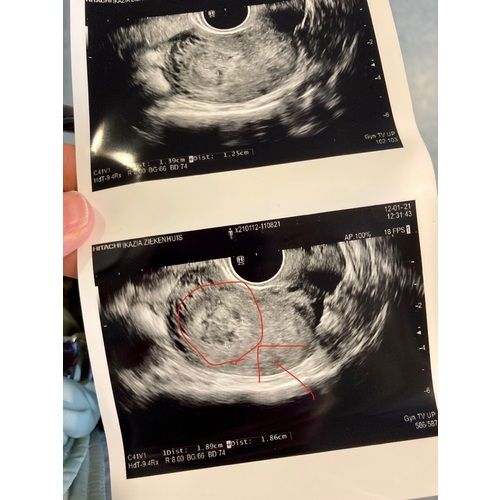

Ik had dat dus ook gehoord, dat vroeg ik vandaag gelijk, maar mijn gynaecoloog zegt dat dat geen effect heeft. Het vruchtje is losgekomen dat ziet hij ook op de echo, het is echt veel weefsel dat over is... afwachten maar... hopelijk dat het tot 17/02 los is dan heb ik weer een controle... mag wek tussentijds bellen als ik alsnog curetage wil als ik mij heel slecht voel.... heel veel succes morgen